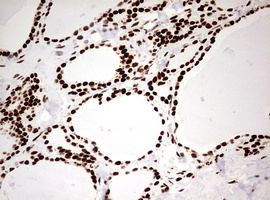

Immunohistochemical staining of paraffin-embedded Human liver tissue within the normal limits using anti-HNRNPM mouse monoclonal antibody. (Heat-induced epitope retrieval by 10mM citric buffer, pH6.0, 120°C for 3min, M06017-2)